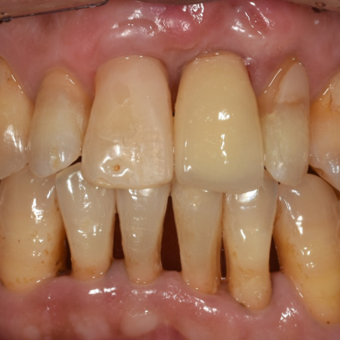

흔들리는 왼쪽 앞니,

임플란트 치료 사례

처음 내원 당시

임시치아

50대 여성 환자분으로, 위쪽 앞니 하나의 치아 뿌리를 잡아주는 잇몸뼈가 완전히 녹고 파괴되어 발치가 불가피한 상태였습니다.

이처럼 잇몸뼈가 퇴축된 경우, 임플란트 치아 길이가 위아래로 길어져 심미성이 떨어지게 됩니다. 추가적인 잇몸이식을 통하여 잇몸의 길이를 확보해 주어야 하는 경우였지만, 환자분께서 잇몸이식을 두려워 하셨고 우선 잇몸 이식 없이 임플란트를 시행하되, 임시치아의 모양을 보면서 차후에 추가적인 잇몸이식을 시행하는 것으로 치료계획을 세웠습니다.